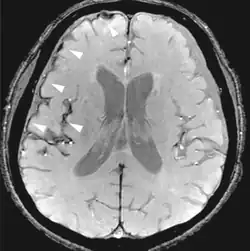

| Fluid-attenuated inversion recovery | FLAIR | Fluid suppression by setting an inversion time that nulls fluids | High signal in lacunar infarction, multiple sclerosis (MS) plaques, subarachnoid haemorrhage and meningitis (pictured).[78] |

| |